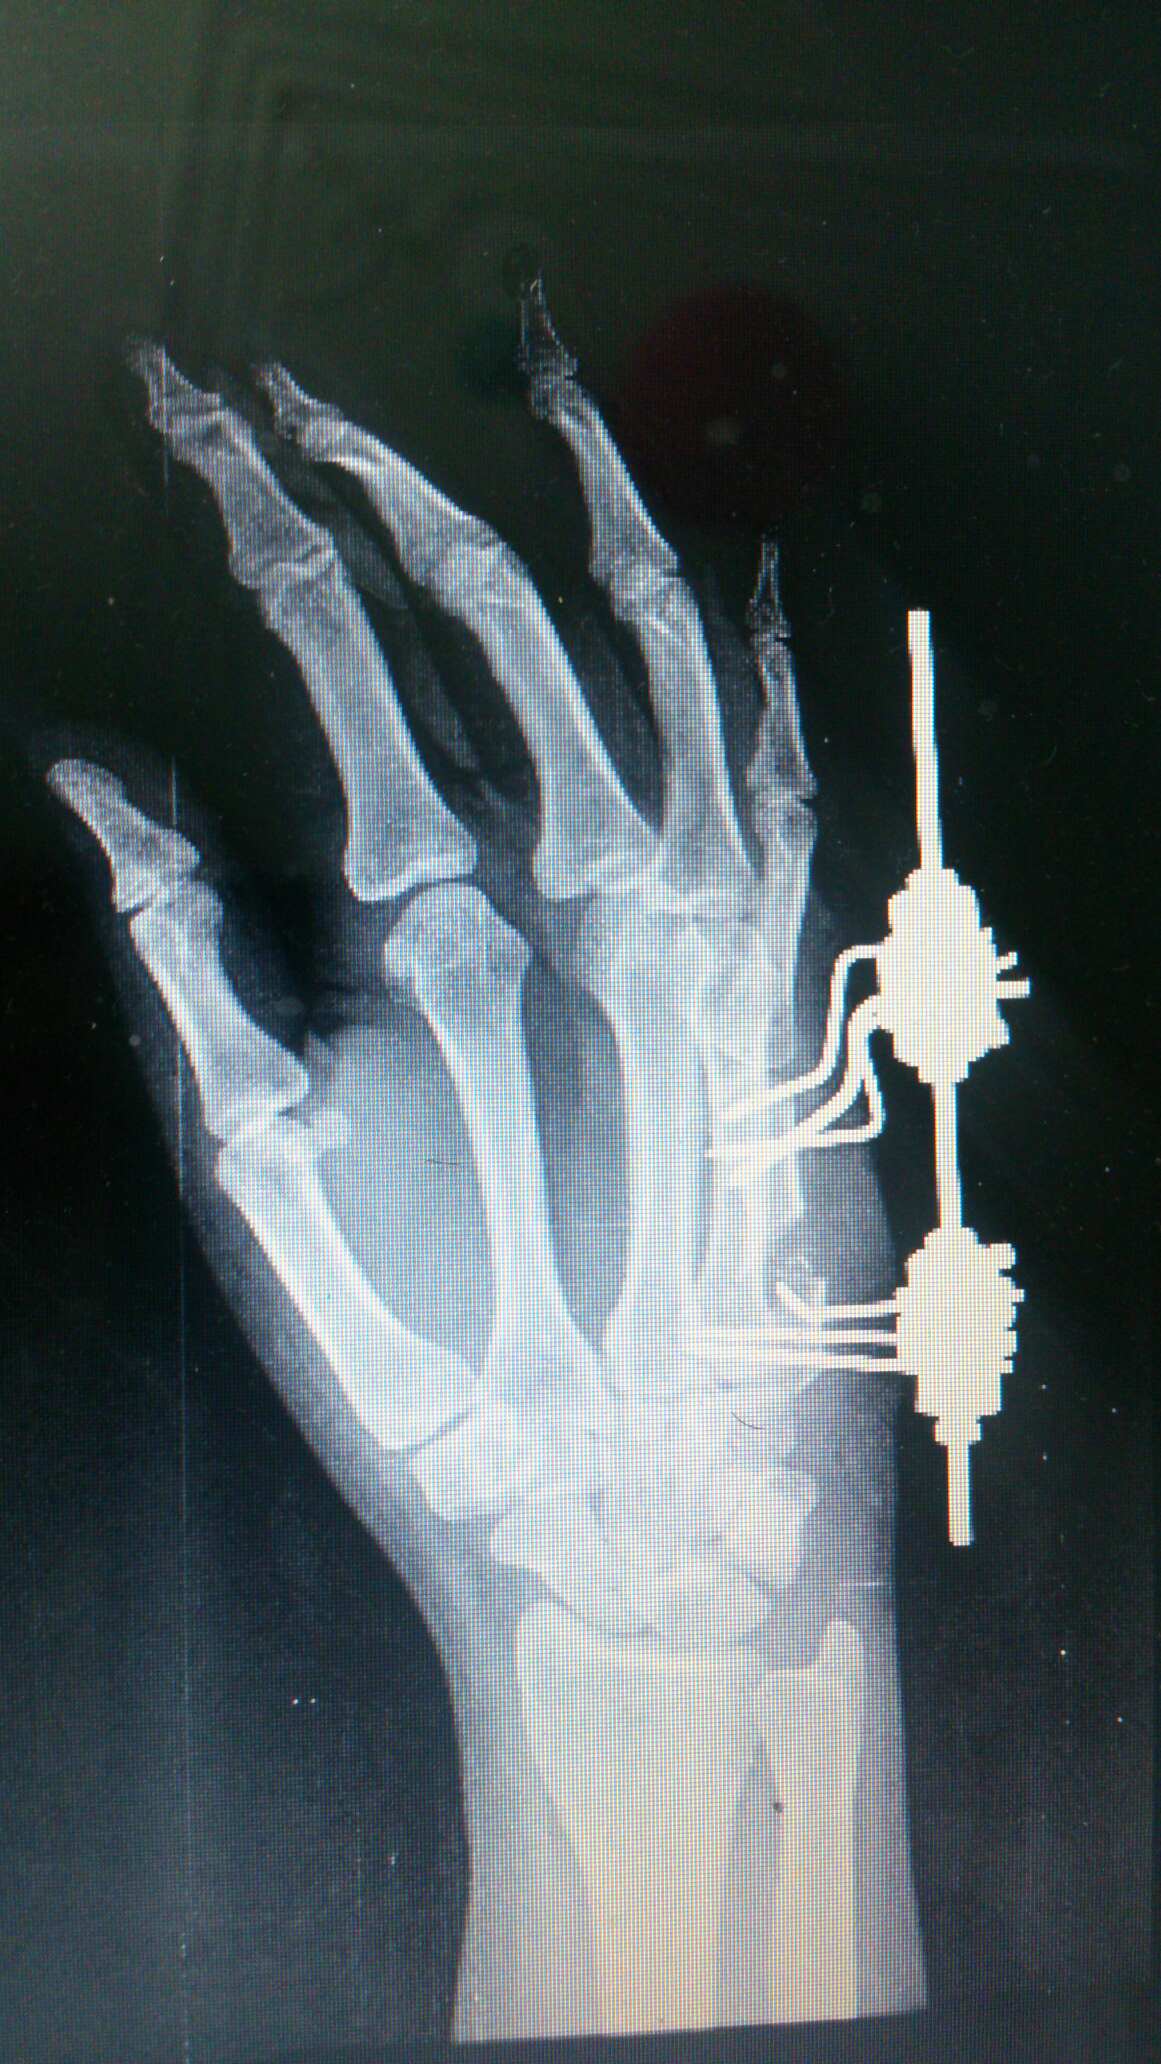

جدید ترین عمل جراحی ایلیزاروف

با همکاری شرکت تجهیزات بهار طب

یکروز بعد عمل

جدید ترین عکس تاریخ 93/8/1